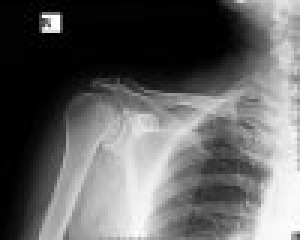

Bu çalışmada amaç;sıkışma sendromuna sebep olmuş Akromioklavikuler(AC) osteoartritli hastalarda,

klavikula distal uç rezeksiyonu uygulamalarımızın fonksiyonel sonuçlarının değerlendirilmesidir.

Bu çalışmada amaç;sıkışma sendromuna sebep olmuş Akromioklavikuler(AC) osteoar...